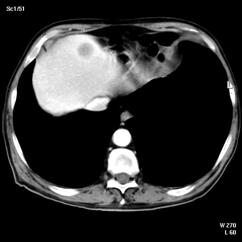

4.3. Tomografia computerizata si rezonanta magnetica nucleara

Informatiile furnizate de aceste metode moderne imagistice ridica procentajul acuratetei diagnostice pana la 85% in aprecierea infiltratiei parietovezicale a tumorilor (T) si la circa 90% pentru decelarea adenopatiei pelviene.

Figura 37. Aspect

tomografic de tumora vezicala. Formatiune tumorala

exofitica protruziva intravezical situata pe peretele

postero-lateral stang. Figura 38. CT pelvin - Tumora voluminoasa in hemivezica

dreapta Figura 39. CT abdominal - Adenopatie extraregionala

periaortico-cava

a. b. Figura 40. Aspect CT - Metastaza

hepatica dintr-o tumora vezicala.